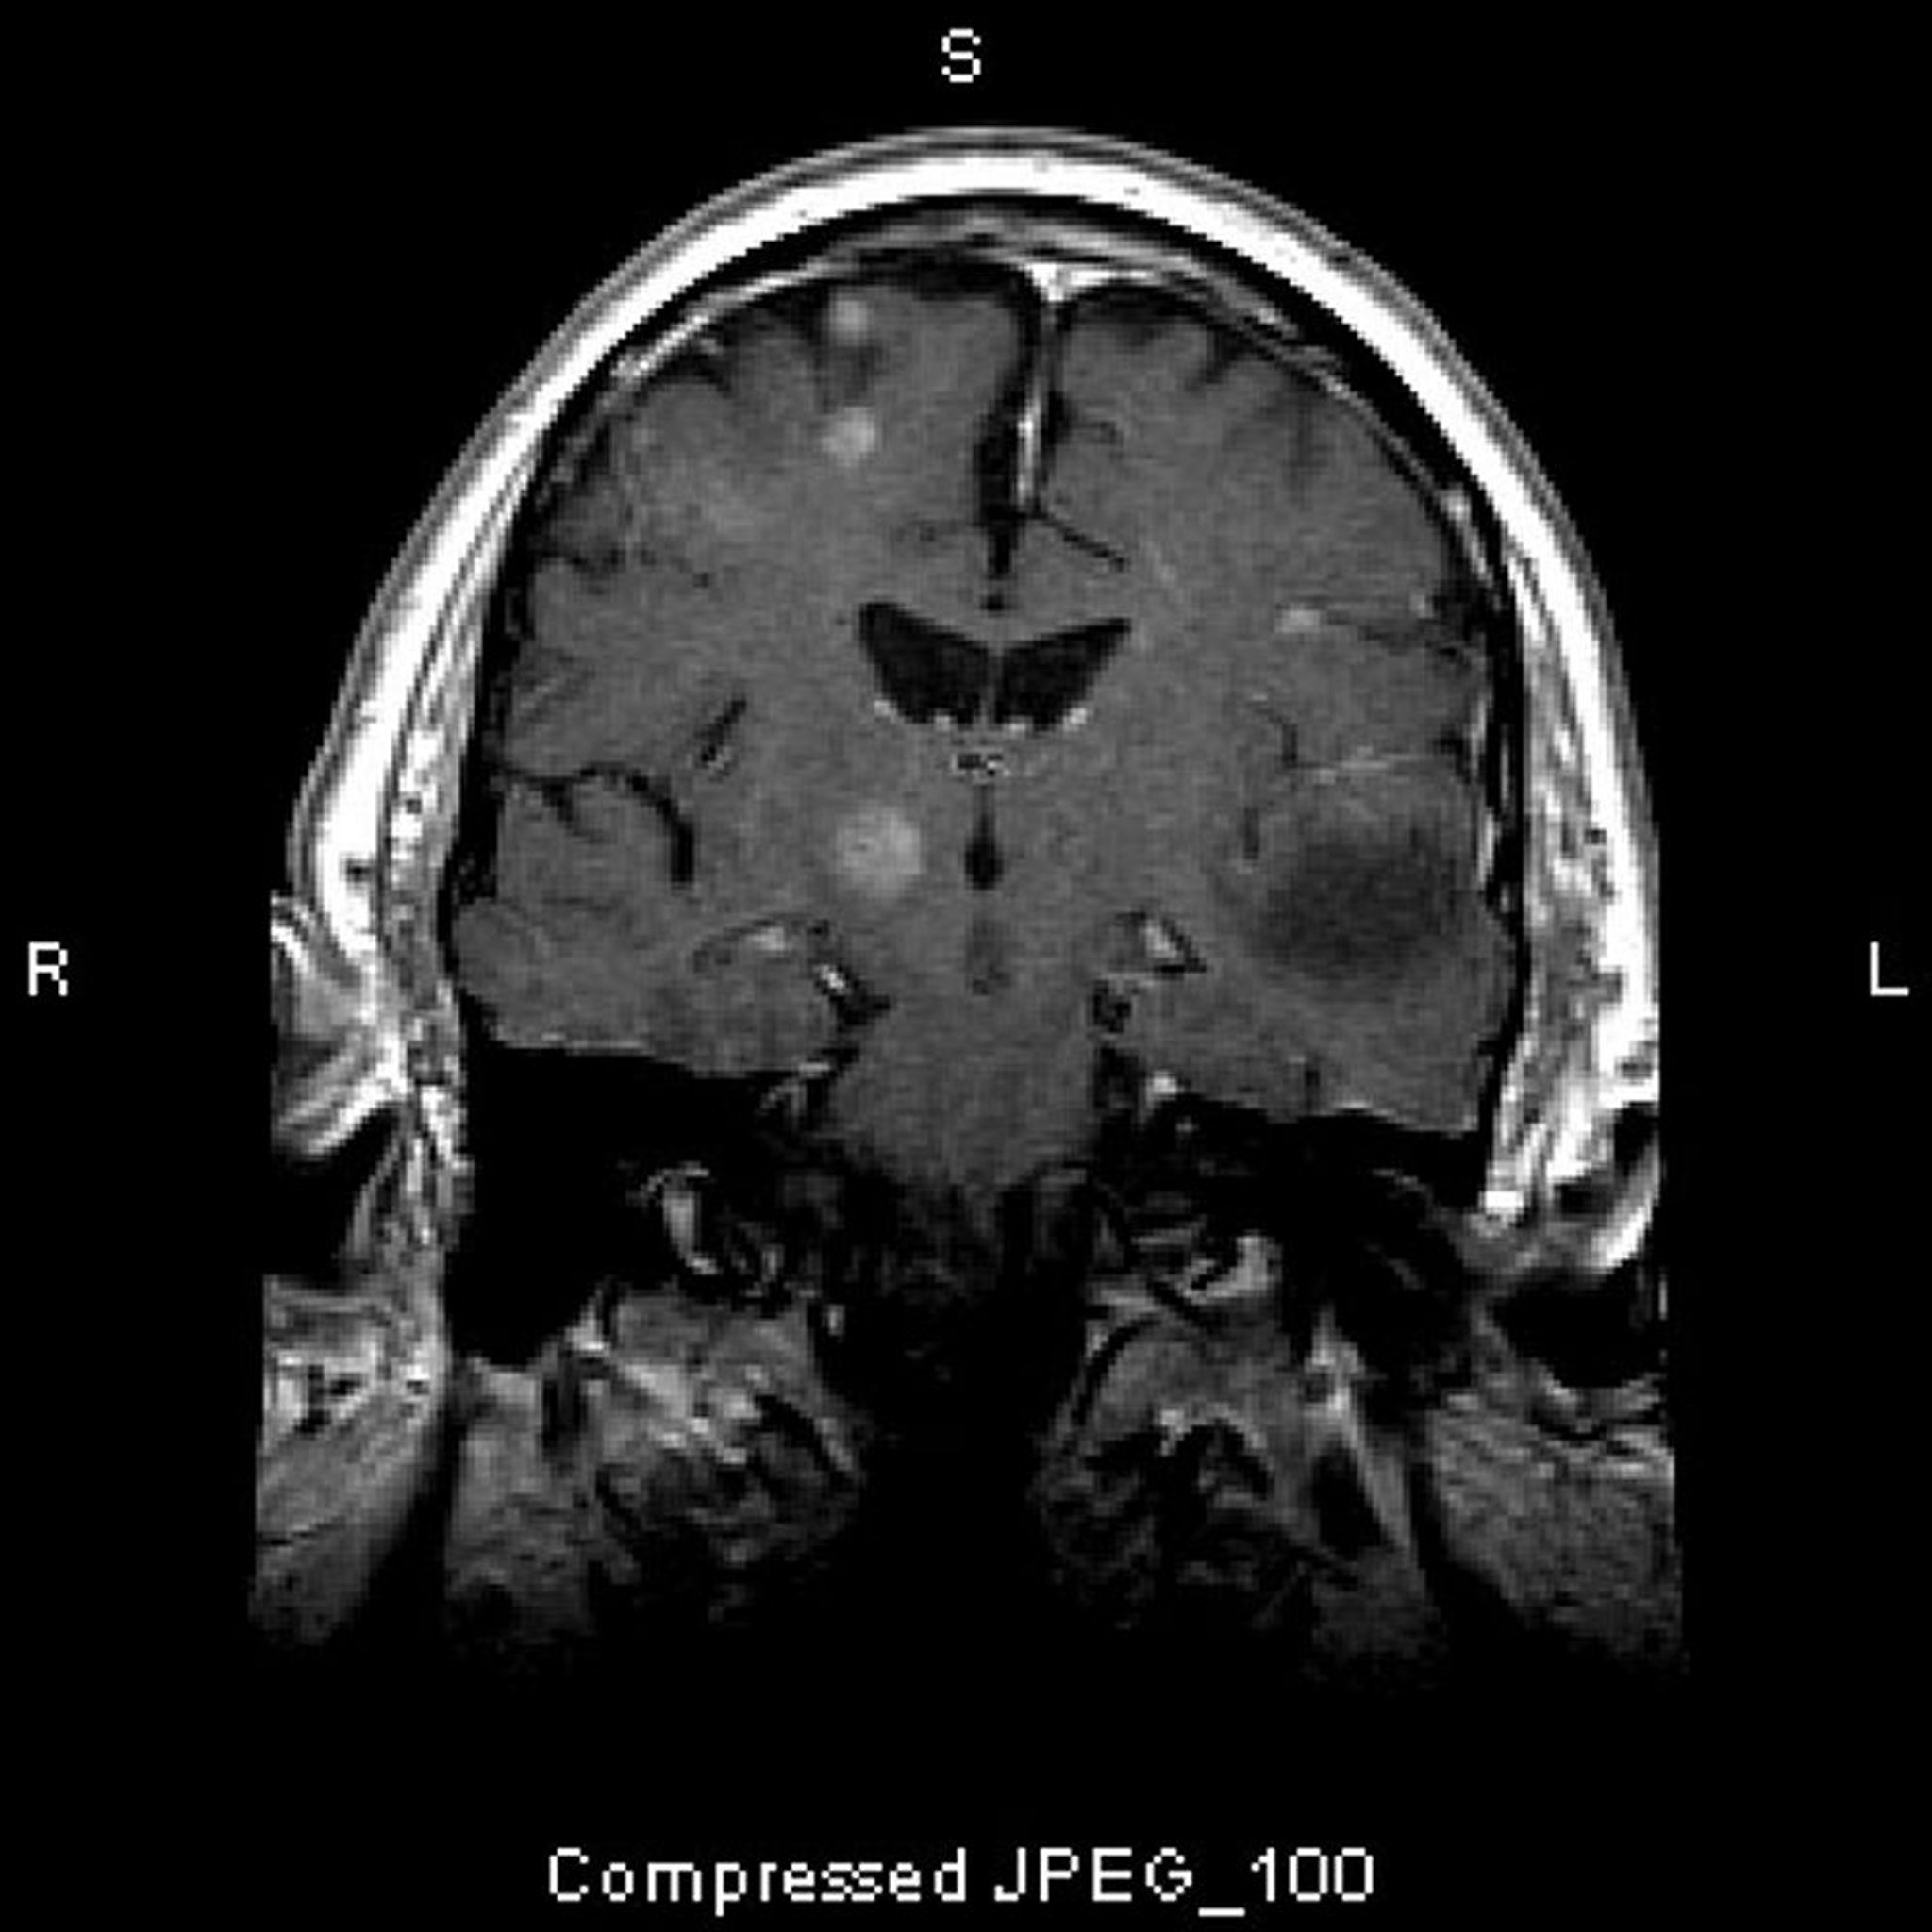

脳転移

このMRIで認められる複数の脳病変は転移性腫瘍である。転移性脳腫瘍の80%以上は多発性である。

Image courtesy of William R.Shapiro, MD.